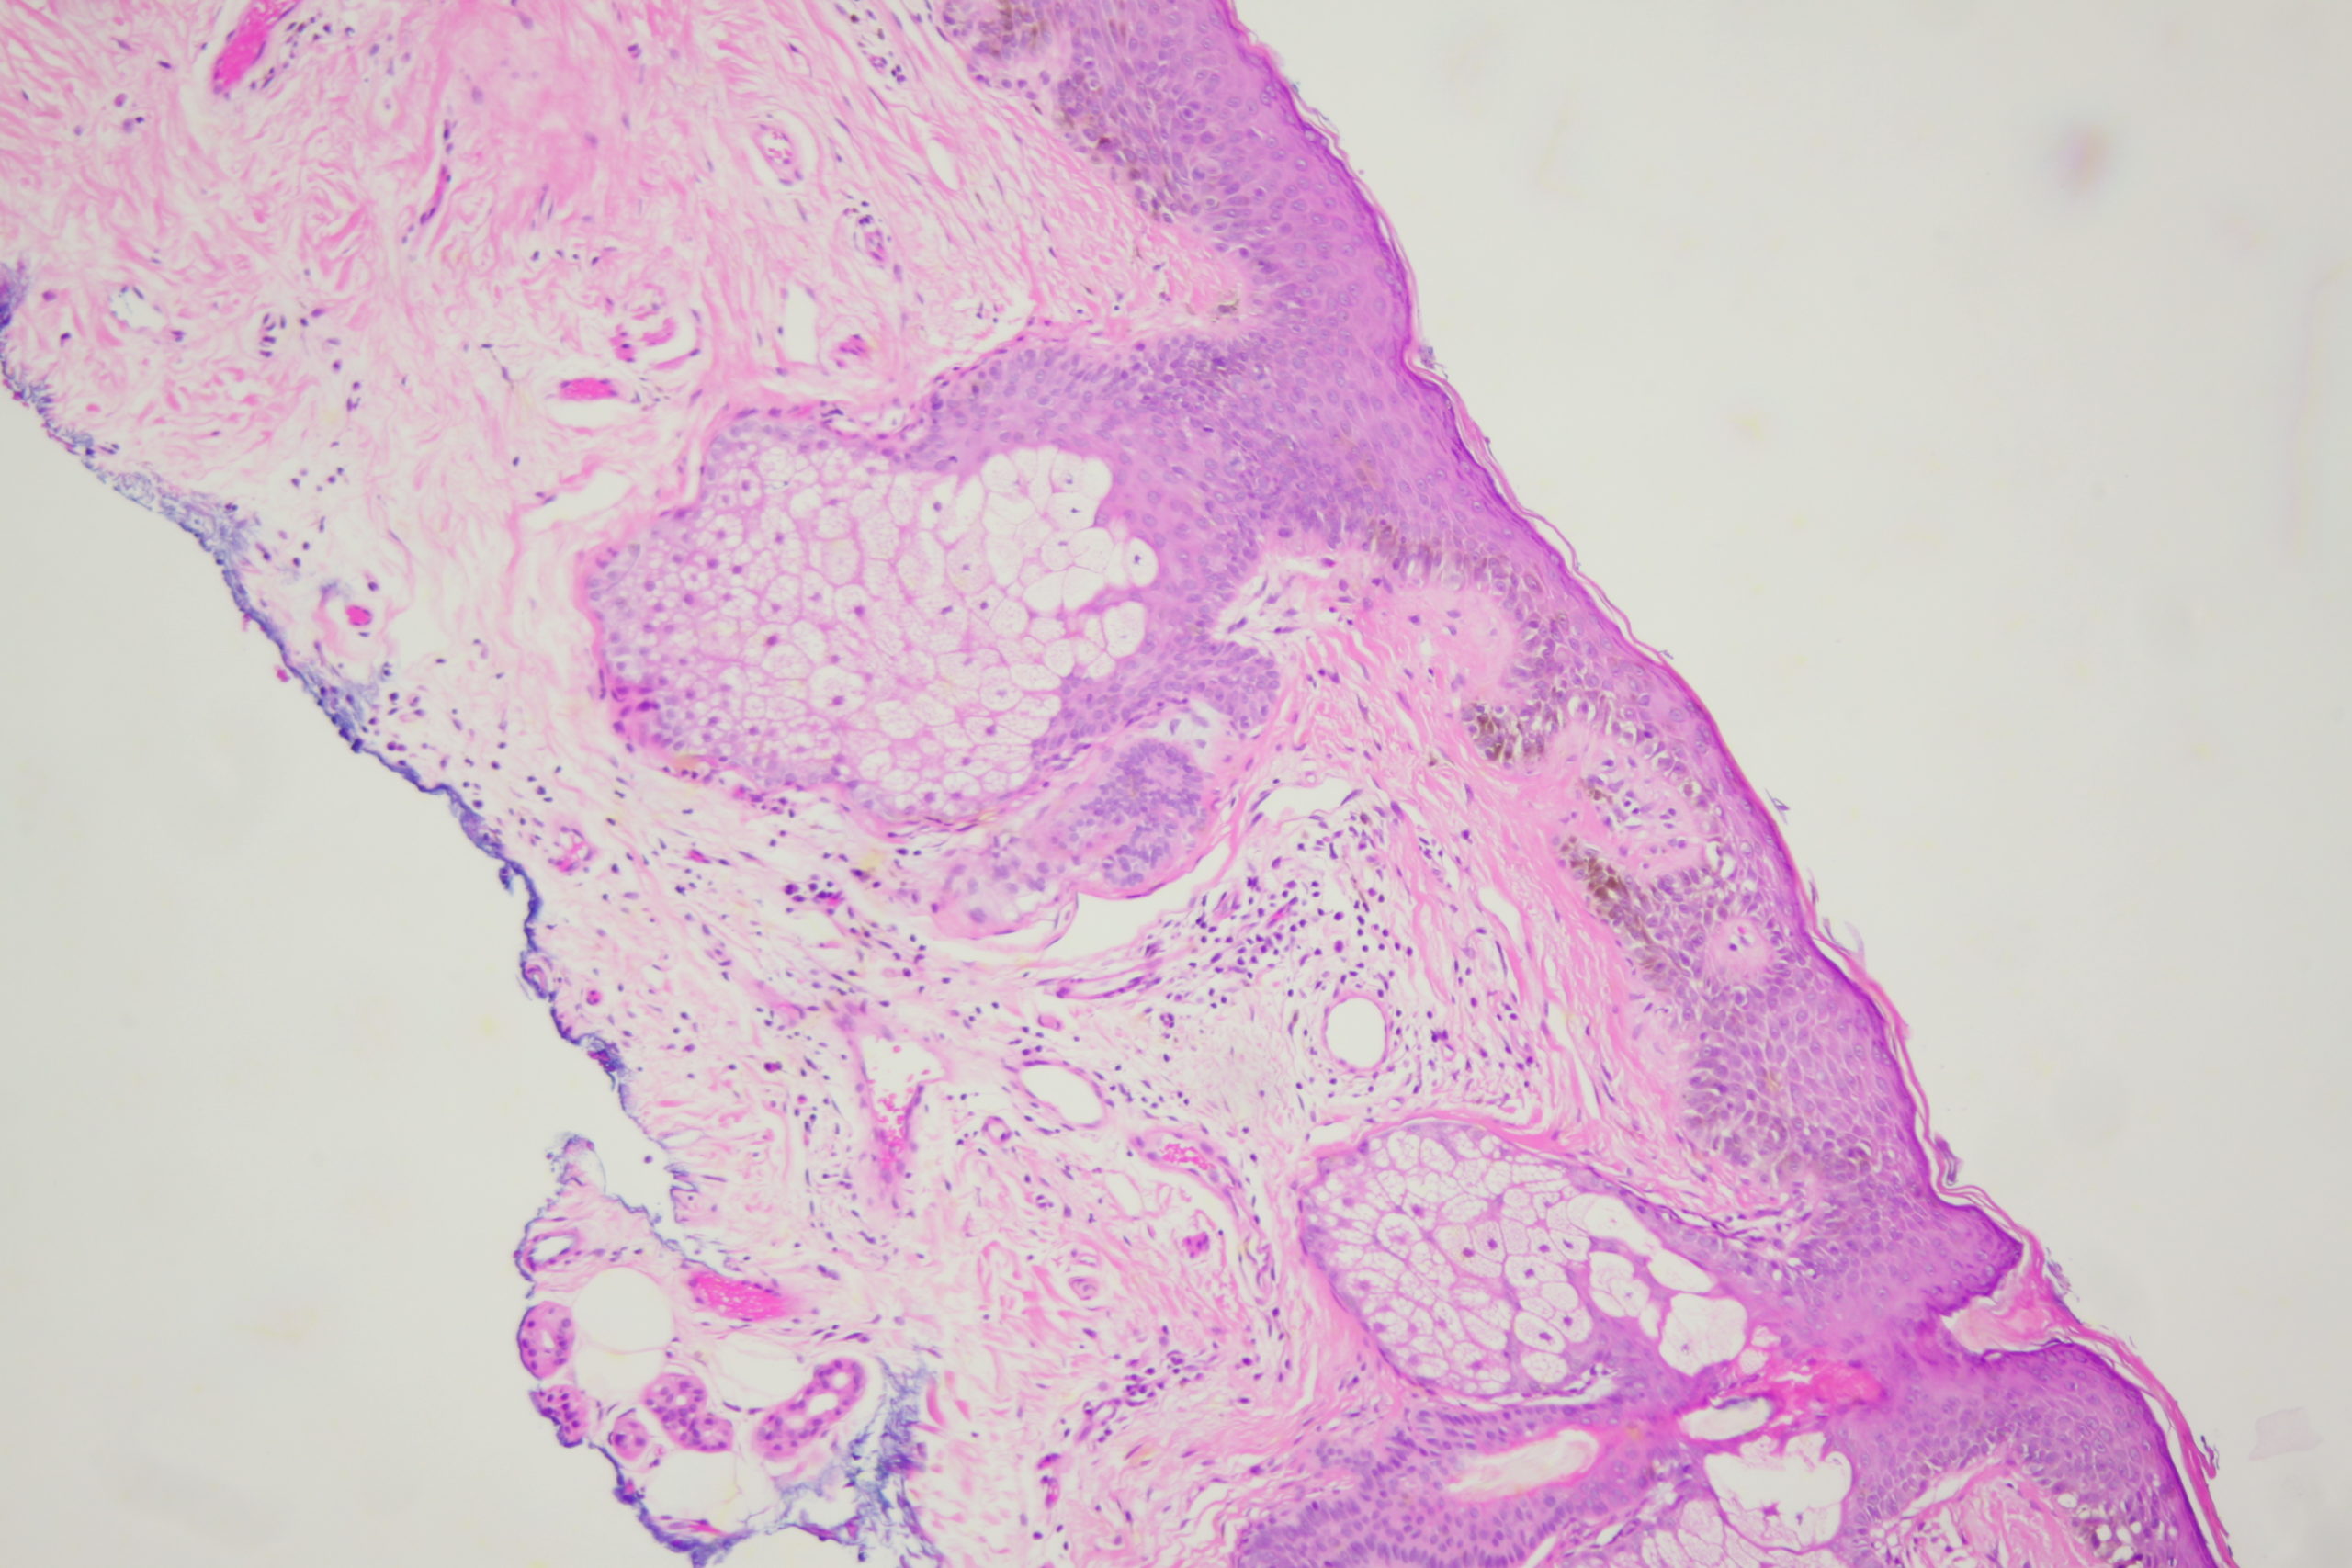

Image Number #3803 (Lentigo Maligna)

Site: Cheek

Diagnosis: Lentigo Maligna

Sex: M

Age: 65

A pigmented lesion on the cheek that has slowly been increasing in size over several years. Male aged 65. Smooth surface.

Dermatoscopy shows pigment dots and pigment around follicles as grey circles. PRAME and Sox 10 showed atypical melanocytes along the DEJ extending into and down follicles with localised upward pagetoid spread. Early Lentigo maligna / Superficial intraepidermal melanoma.